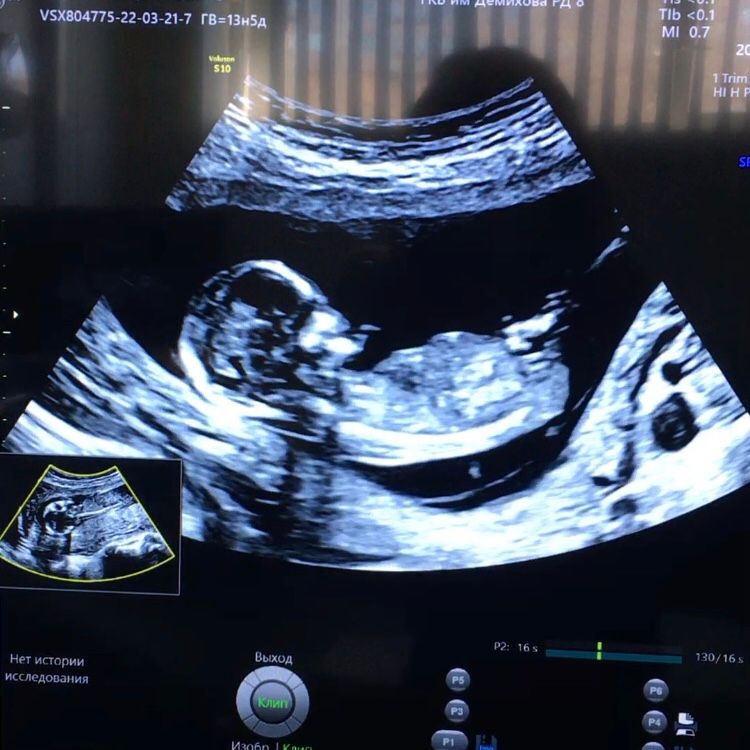

Вообще, не видно😅 но предположу мальчика, просто так вот мне кажется😁

Думаю девочка, да и череп аккуратный как у девочек. Половой бугорок вроде лежит

Анастасия, можно и я у вас спрошу, вижу по количеству деток понимаете по фото)) этот бугорок как лежит то? Там же по спине как то смотрят ещё? У автора прям лежит а тут не пойму

Алекса, как мне видится, что тут девочка тоже😊бугорок не торчит, лежит же вроде😇

Алекса, я в этом не разбираюсь, поэтому выложила, вдруг кто что-то заметит)) но мне кажется на последнем ножка